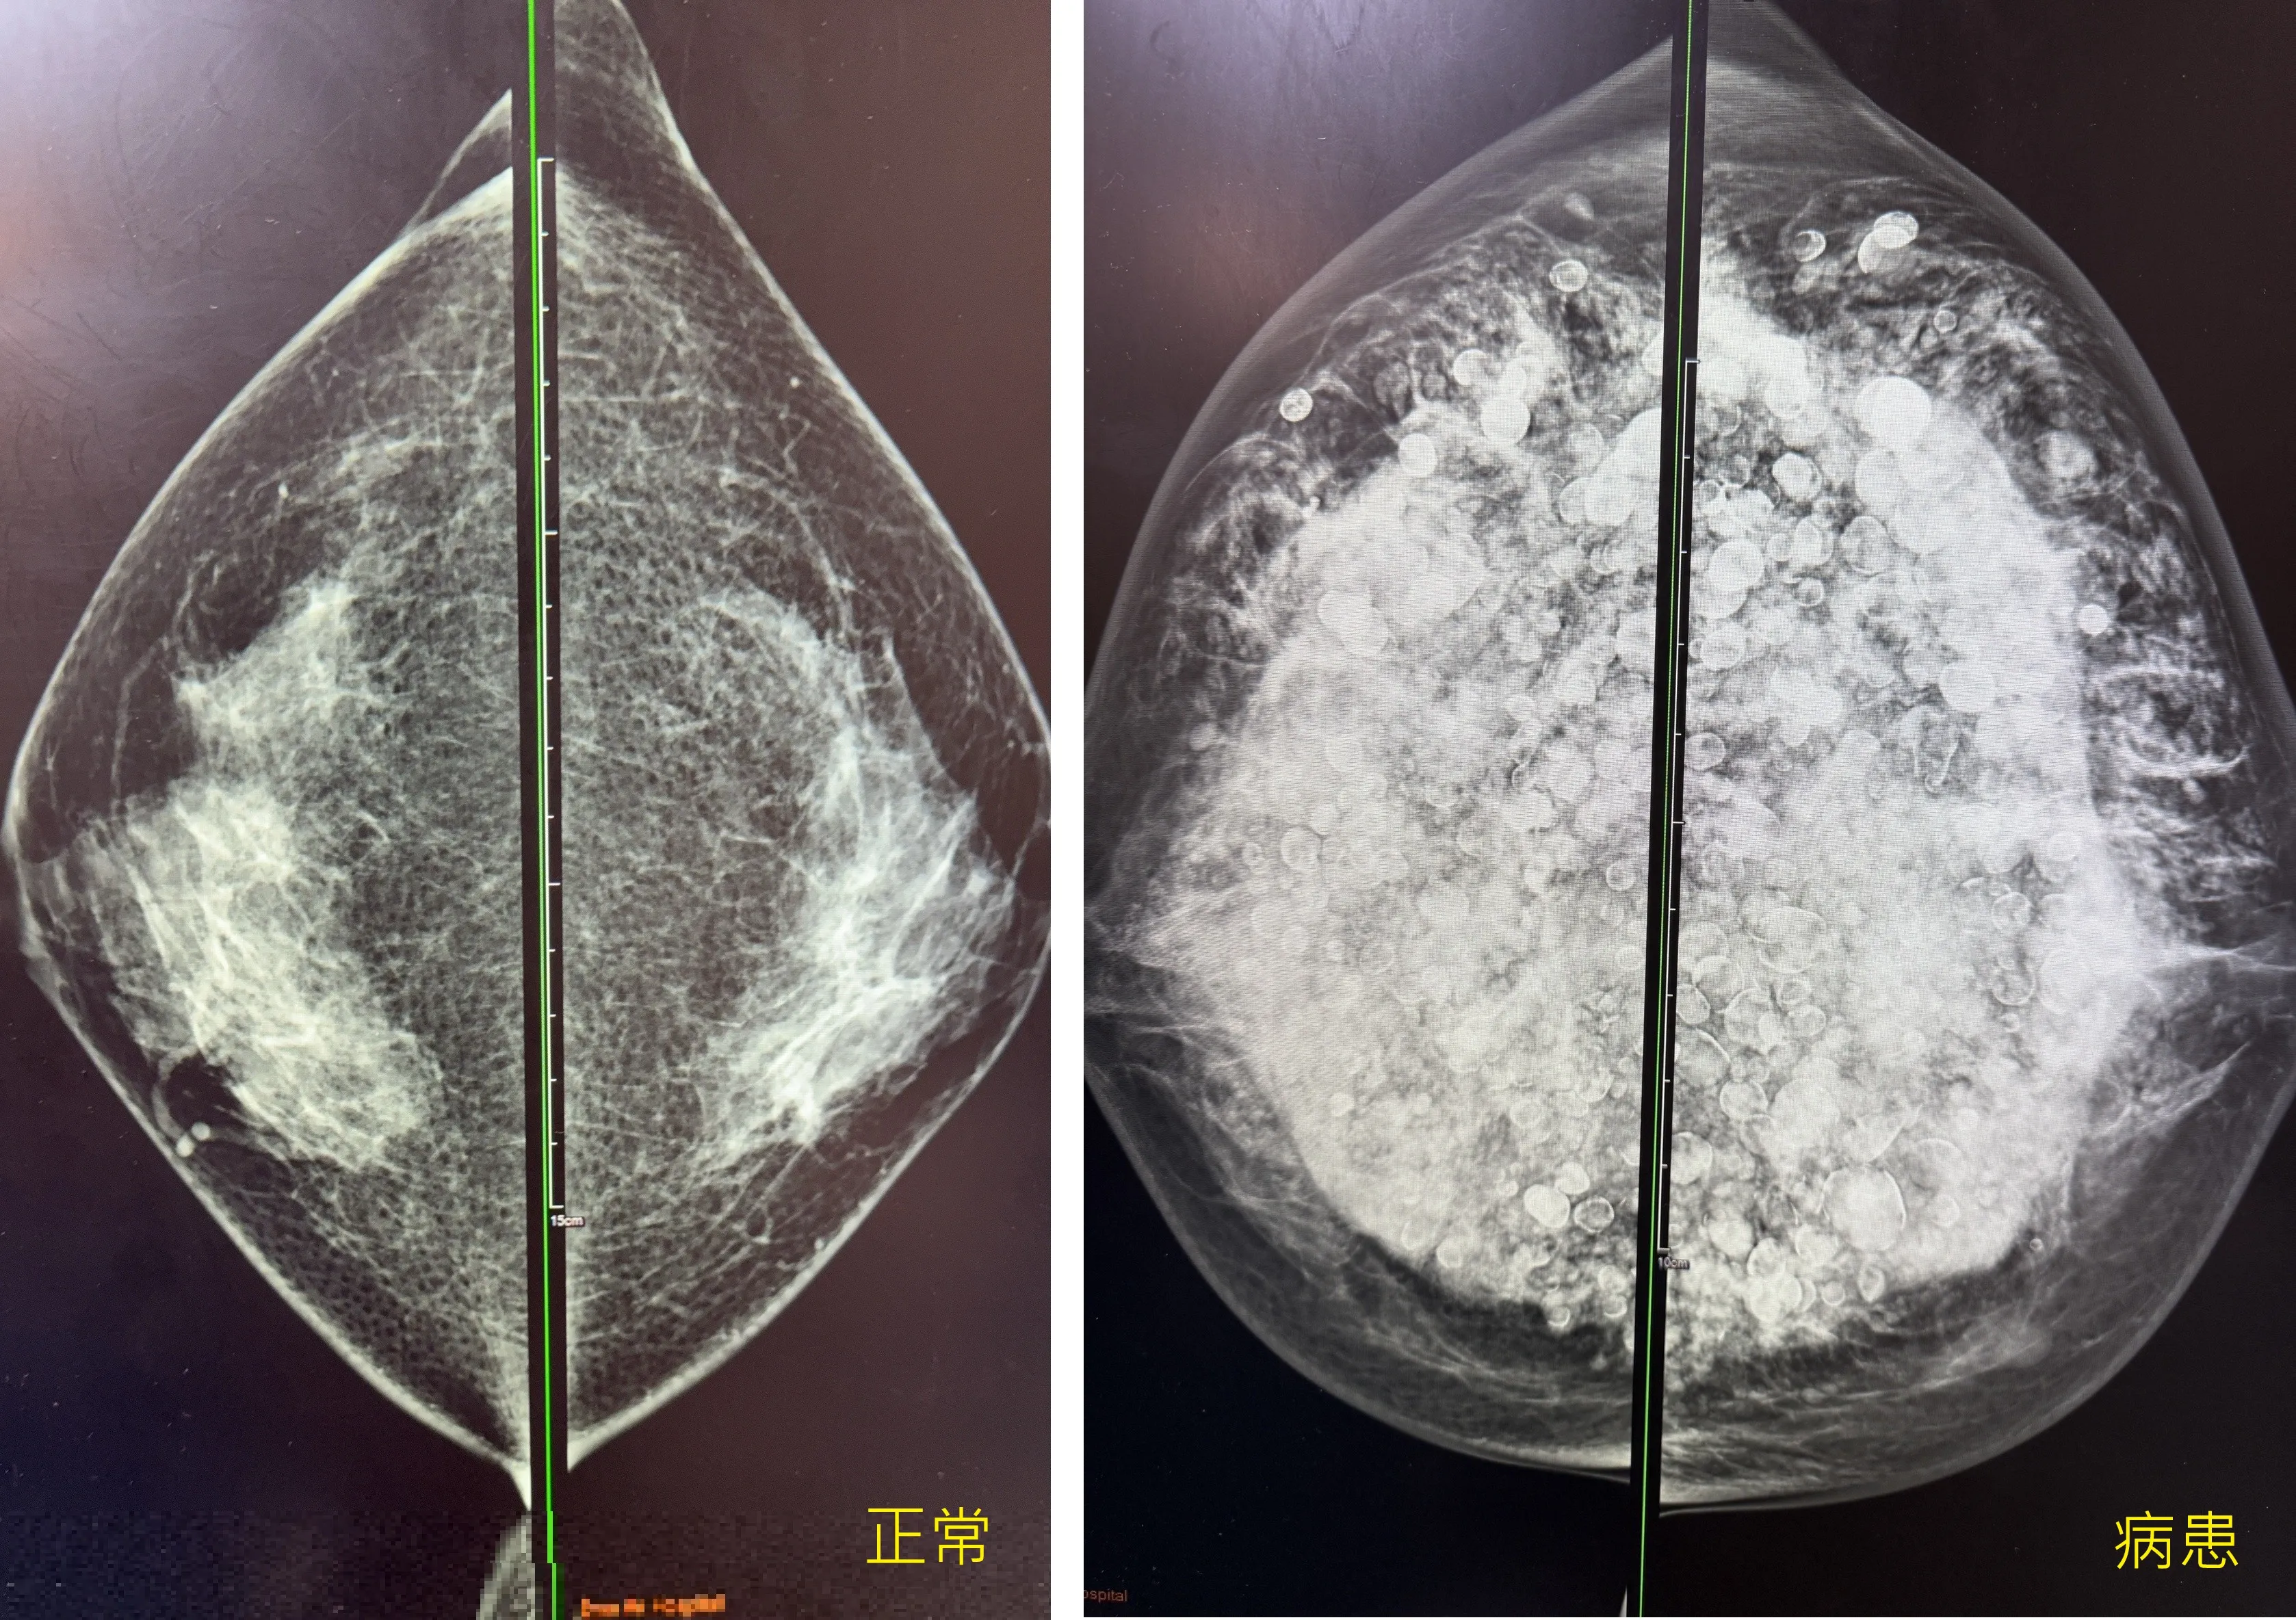

陳女士的乳房攝影圖(右圖)對比健康的乳房攝影(左圖)充滿鈣化和發炎組織。